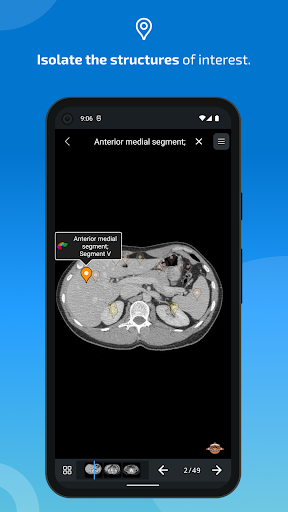

* تحسين عرض التفاصيل للأجزاء التشريحية لتسهيل التعرف عليها في صور الوحدات الحالية والوحدات الأخرى.

- يتميز وضع الدبابيس بسلوك جديد يسمح لك باتباع بنية تشريحية بسهولة أكبر

- ضمن عرض التفاصيل للبنية التشريحية ، يشير الدبوس الآن إلى البنية ذات الصلة في جميع الصور الحالية

انقر أيضًا مباشرة على الصورة للانتقال إلى الصورة المعروضة في تلك الوحدة